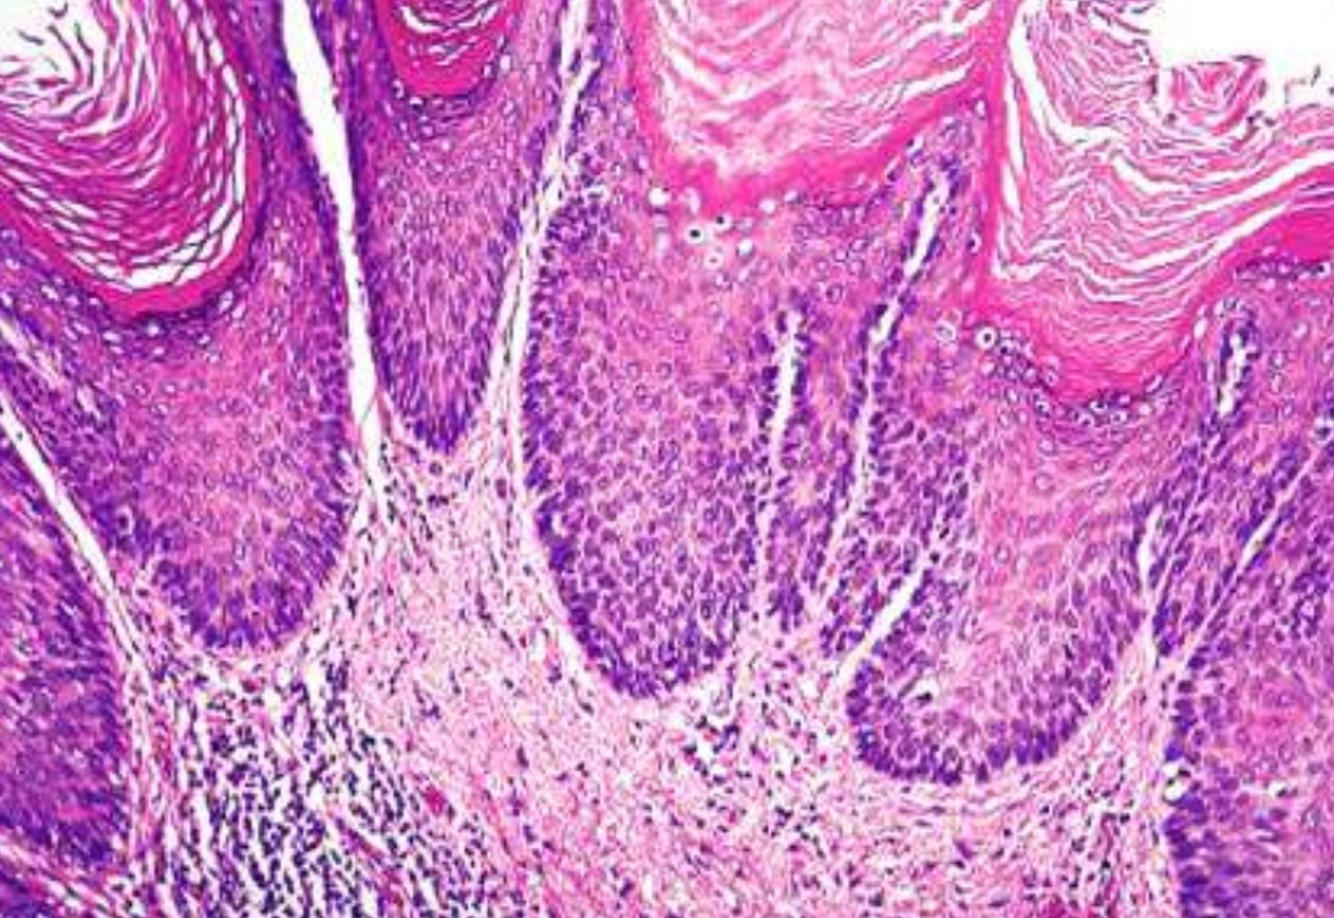

VULVAR INTRAEPITHELIAL NEOPLASIA

• HPV associated type

• Younger age

• Multifocal

• CIN

• Smoking

• HPV negative type

• Associated with vulvar inflammatory disease (LS)

• Older age

• Unifocal

• Associated with p53 mutations

• Well differentiated simplex VIN